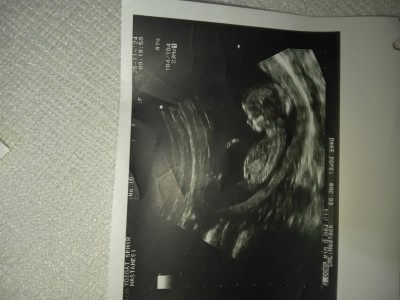

Cinsiyet Tahmini: Bu Görseldeki Canlının Cinsiyeti Nedir?

s.sizce cinsiyeti nedir?

İçimden erkek geldi :)

Bence erkek:)

Erkeğe benziyor sanki canım içimden öyle geçti görünce

Kesinlikle kız duruşu var minnakta ,:)

İçimden erkek geçti ama yüzü kıza benziyor kaç haftalık canm bebeiş

Çok narin bı duruşu var bence kız

Benimde içime erkek doğdu.. Sağlıcakla kucağına al inşallah... Allah yardım etsin

Kız canm Allah bağışlasın

Bence erkek canım